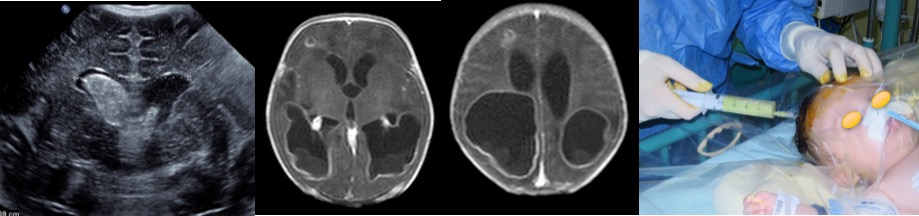

- les abcès du nouveau-né, dans un contexte de méningite néonatale ou d’infection sur cathéter

chez le nouveau-né

on peut réaliser une ponction percutanée au lit du patient en réanimation (Cf. ci-dessus), qui peut être utilement guidée par l’échographie (Cf. ci-dessous)

elle consiste au minimum en une ponction de l’abcès, par trépanation, éventuellement guidée par neuronavigation, ou par ponction trans-fontanellaire éventuellement sous contrôle échographique. il s’agit le plus souvent d’une urgence chirurgicale en raison du risque d’aggravation rapide au plan neurologique comme au plan infectieux.

chez le nourrisson, le pronostic développemental est très réservé en raison de la gravité de la méningite initiale, du terrain pré-existant, et des complications ultérieures comme l’hydrocéphalie cloisonnée et l’épilepsie pharmaco-résistante.